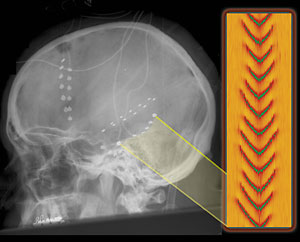

A lateral skull radiograph of an epilepsy patient with a series of electrodes implanted into his brain by Dr. Nicholas Barbaro at UCSF. The electrodes allowed neurologists to map the electrical activity produced during the patient's seizures in preparation for brain surgery. The inset at right highlights the mathematical model of the electrical waves, which was compared with the actual readings from the two electrodes noted.

Before surgery, neurologists needed to map the region where the patient's seizure originated to ensure that they only remove what is necessary. To help neurologists observe the patient's seizures, 64 electrodes were implanted into his brain for a week. The researchers were thus able to obtain data from six of the patient's seizures to compare with the mathematical model they had created.

The researchers focused on two subdural electrodes spaced a centimeter apart on the surface of the patient's brain. They noticed a consistent delay of 25 milliseconds in electrical peaks between the two electrodes, indicating a strong, coherent wave pattern characteristic of a seizure.

"The wave signals from both the model and the observational data were similar in shape, frequency and speed of propagation," said Kramer. "That suggests that our model is pretty accurate."